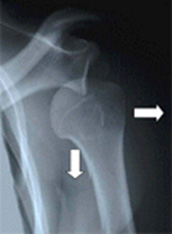

Η διάγνωση του τραυματικού εξαρθρήματος του ώμου επιτυγχάνεται με την κλινική εξέταση και τον ακτινολογικό έλεγχο. Συχνά βέβαια, η κλινική εξέταση είναι ιδιαίτερα επώδυνη γι αυτό και επί υποψίας εξαρθρήματος συνιστάται άμεσος ακτινολογικός έλεγχος. (Εικ. 2)

Ο ακτινολογικός έλεγχος που απαιτείται είναι απλή ακτινογραφία ώμου σε δύο επίπεδα (προσθιοπίσθια και διαμασχαλιαία)